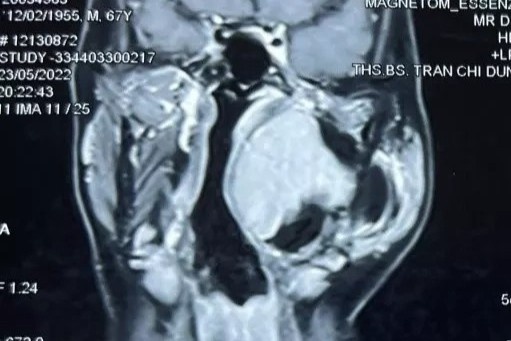

May mắn hơn là trường hợp nam bệnh nhân 70 tuổi ở Hà Nội. Người này có tiền sử nghiện thuốc lá. Khi vào viện, ông bị đau chân, đi lại khó, thi thoảng đau nhói như chuột rút. Hình ảnh chụp mạch máu cho thấy bệnh nhân bị động mạch vôi hóa trắng xóa do tiền sử hút thuốc kèm theo xơ vữa động mạch. Bác sĩ đã cố gắng điều trị để bảo tồn chân lâu nhất cho người bệnh.